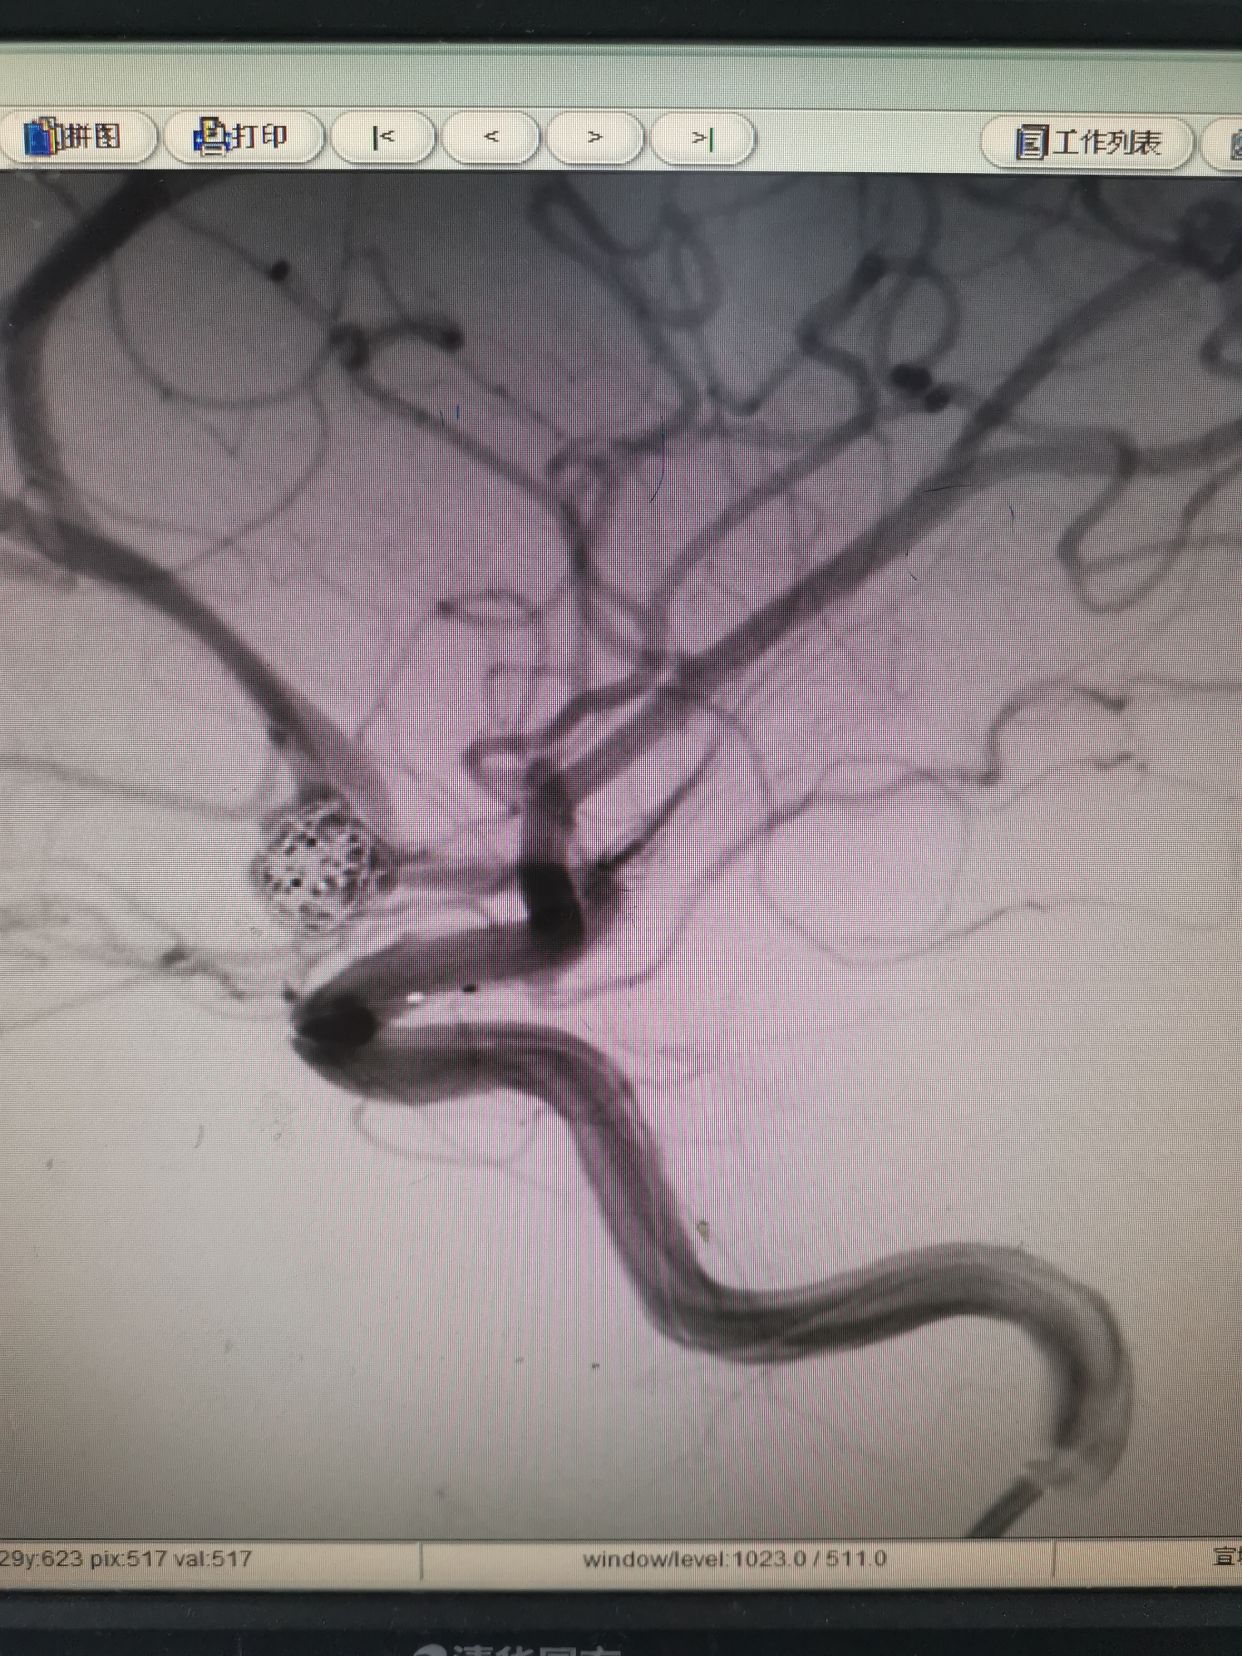

右侧颈内动脉造影。

左侧颈内动脉造影,发现一宽颈前交通动脉瘤。